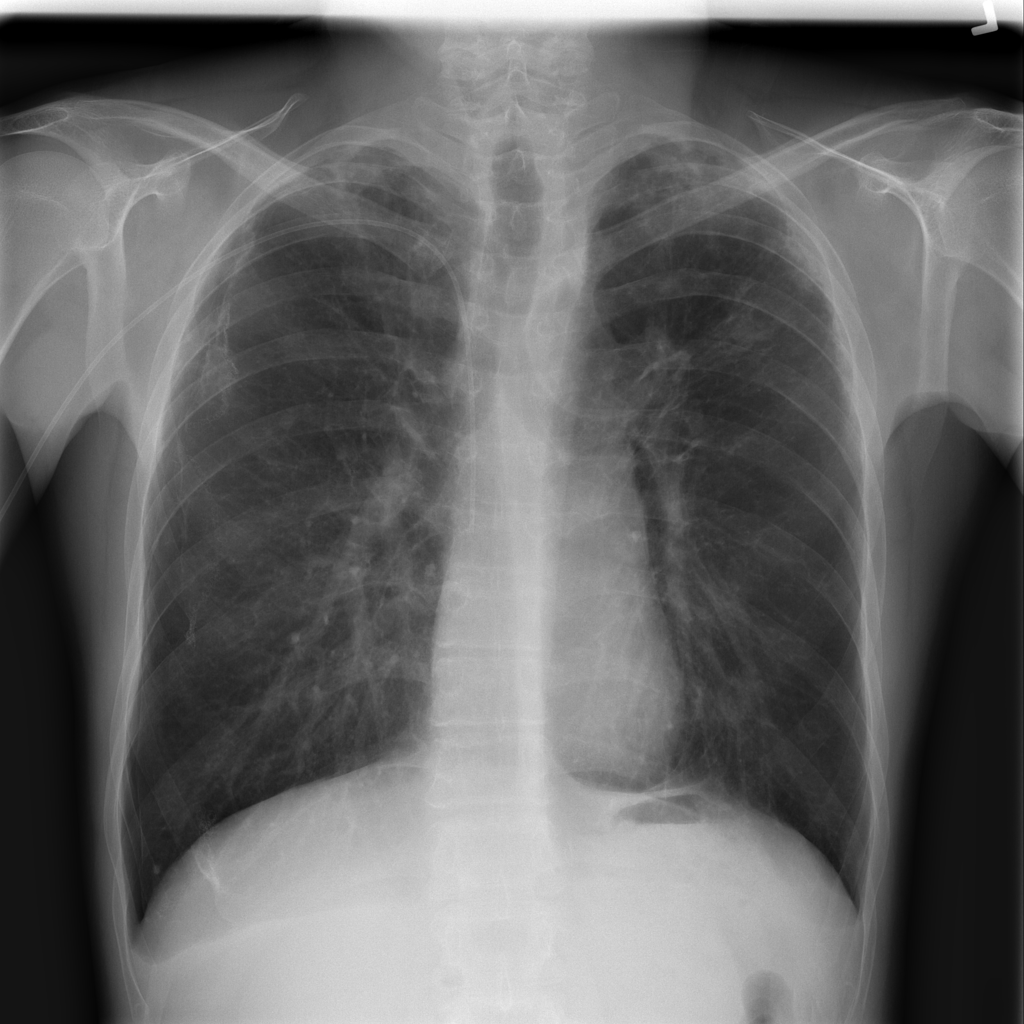

PAT-4639 · IMG-020Pneumothorax

PAT-4639 · IMG-020

PA